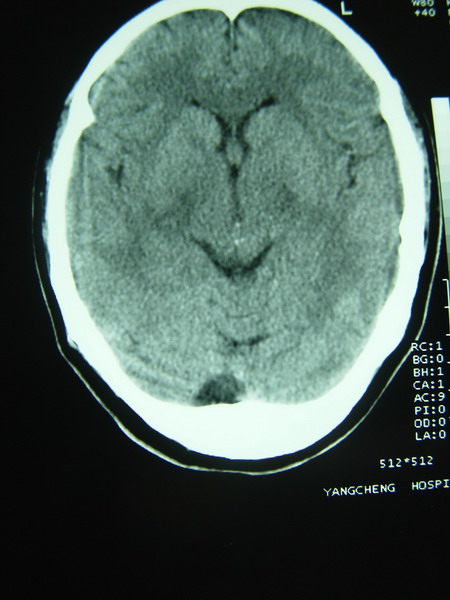

标题: CT12368:女,44岁。突发性左侧肢体麻木4天。 [打印本页]

标题: CT12368:女,44岁。突发性左侧肢体麻木4天。

右侧基底节区腔隙性脑梗塞;右侧顶叶深部及放射冠区病灶考虑机器伪影所致,建议ct增强扫描。

看到黑箭所致的类圆形图形了吧?周围是低密度环形影,用腔隙梗塞来解释很难令人信服。

1确实看到环状低密度影,看症状支持梗塞,最好增强下

2大枕大池?还是脂肪浸润?

枕大池蛛网膜下腔囊肿。右侧半卵圆中心占位性病变,建议强化

应该是机器伪影吧(做一个空气校正或薄层扫描可以改善)。如果是病灶,没有占位效应(排除占位性病变),有4天病史的梗塞灶应该是低密度改变。

右侧半卵圆中心占位性病变,建议强化

但从症状支持脑梗塞诊断,但右侧半卵园中心“影”确实用梗塞及占位都不好解释,可以做一下机器校正后薄层扫描。

枕大池蛛网膜下腔囊肿。右侧半卵圆中心占位性病变。